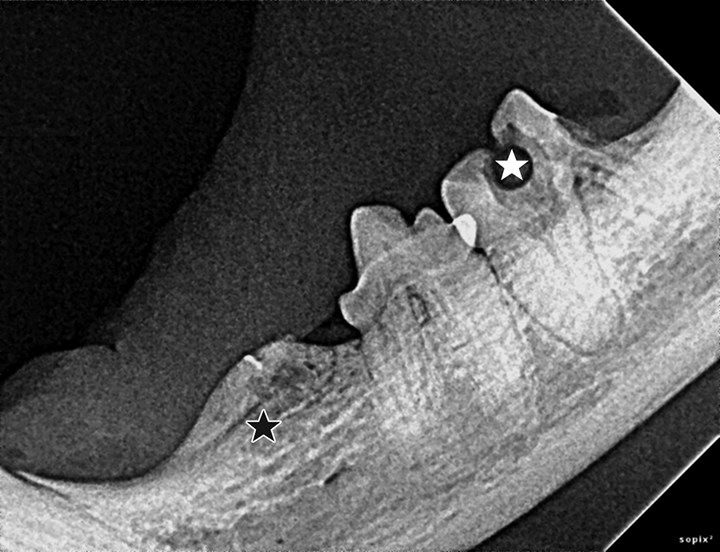

Dental Radiography Taking the Xrays OSU CVM Veterinary Clinical Dental Radiographs Practice the american dental association (ada) has various policies and recommendations to help dentists ensure that patients’. the european academy of paediatric dentistry (eapd) proposes this best clinical practice guidance to help. quiz yourself with questions and answers for dental radiology practice test, so you can be ready for test day. This article provides the fundamentals of. . Dental Radiographs Practice.